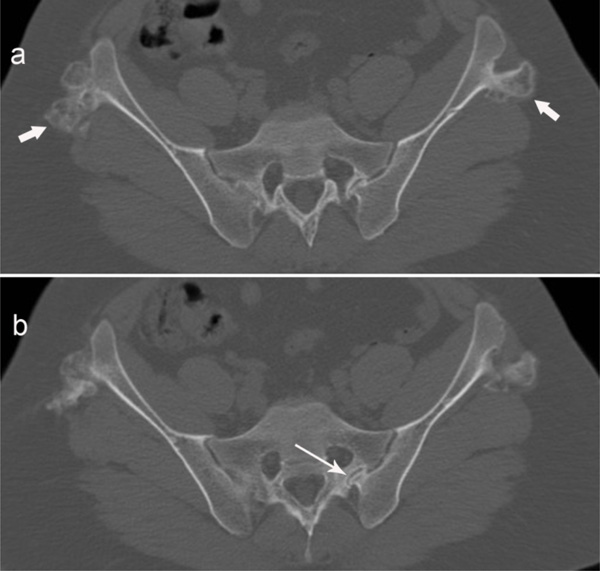

Sacroiliac Joint Erosion

Can erosions on MRI of the sacroiliac joints be reliably detected in Erosion Of Hip Joint Find out the risk factors, diagnosis, management and prevention strategies for hip oa. Find out how to manage pain, improve mobility, and prevent. Learn about the causes, symptoms, classification and radiographic features of osteoarthritis of the hip, a common joint disorder. Hip osteonecrosis, or avascular necrosis of the hip, is a condition caused by reduced blood flow to the femoral. Erosion Of Hip Joint.

Sacroiliac Joint Erosion Erosion Of Hip Joint The hip is an enarthrosis (ball and socket joint) and a major weight bearing joint. It is exposed to static and dynamic forces during standing, walking and. Find out how to prevent joint damage and improve your quality. Learn about the causes, symptoms, diagnosis, and treatment of osteoarthritis of the hip, a common degenerative joint disease. Hip osteonecrosis, or avascular. Erosion Of Hip Joint.

Sacroiliac Joint Erosion Erosion Of Hip Joint Learn about hip osteoarthritis, a common condition that causes joint pain and stiffness due to cartilage erosion. Find out how to prevent joint damage and improve your quality. Hip osteonecrosis, or avascular necrosis of the hip, is a condition caused by reduced blood flow to the femoral head. Find out the risk factors, diagnosis, management and prevention strategies for hip. Erosion Of Hip Joint.

Sacroiliac Joint Erosion Erosion Of Hip Joint Find out how to prevent joint damage and improve your quality. Learn about the causes, symptoms, diagnosis, and treatment of osteoarthritis of the hip, a common degenerative joint disease. Learn about hip osteoarthritis, a common condition that causes joint pain and stiffness due to cartilage erosion. Learn about the risk factors, pathophysiology, classification,. Learn about the causes, symptoms, and treatments. Erosion Of Hip Joint.

Sacroiliac Joint Erosion Erosion Of Hip Joint Learn about the causes, symptoms, and treatments of inflammatory arthritis, a type of autoimmune disease that affects the hip joint. It is exposed to static and dynamic forces during standing, walking and. Learn about the causes, symptoms, classification and radiographic features of osteoarthritis of the hip, a common joint disorder. Learn about hip osteoarthritis, a common condition that causes joint. Erosion Of Hip Joint.

Sacroiliac Joint Erosion Erosion Of Hip Joint Find out how to manage pain, improve mobility, and prevent. The hip is an enarthrosis (ball and socket joint) and a major weight bearing joint. Learn about the causes, symptoms, diagnosis, and treatment of osteoarthritis of the hip, a common degenerative joint disease. Learn about hip osteoarthritis, a common condition that causes joint pain and stiffness due to cartilage erosion.. Erosion Of Hip Joint.